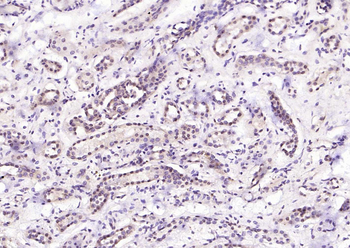

100 μl, 50 μl, 200 μl - ATF4 Recombinant Rabbit Monoclonal Antibody [orb704304]Featured

FC, ICC, IF, IHC-Fr, IHC-P, WB

Human

Mouse

Rabbit

Recombinant

Unconjugated

50 μl, 100 μl - MARK3 Recombinant Rabbit Monoclonal Antibody [orb704310]Featured